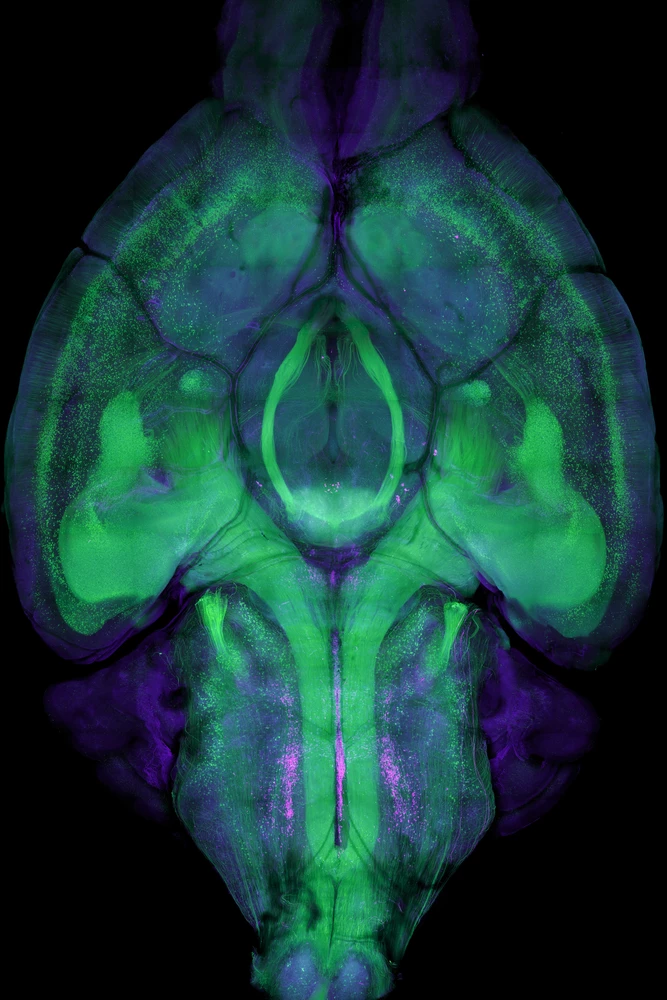

This image is a 1.5-millimeter-thick horizontal slice through the brain of a mouse. It shows the neurons that produce serotonin in purple (1) and pyramidal neurons in green (2).

Pyramidal neurons are one of the most common types of neurons in the brain and are so named because of their pyramid-shaped cell bodies. These neurons are involved in a wide range of cognitive functions, including memory, movement, the processing of sensory information, and much more.

Many pyramidal neurons have serotonin receptors and may therefore be involved in controlling mood and emotions.

Serotonergic neurons vary in size but on average have cell bodies that are about 38 microns across, or roughly half the width of a human hair. Pyramidal neurons also vary in size but on average have cell bodies that are about 20 micrometers across, or roughly 3.5 times smaller than the width of a human hair.